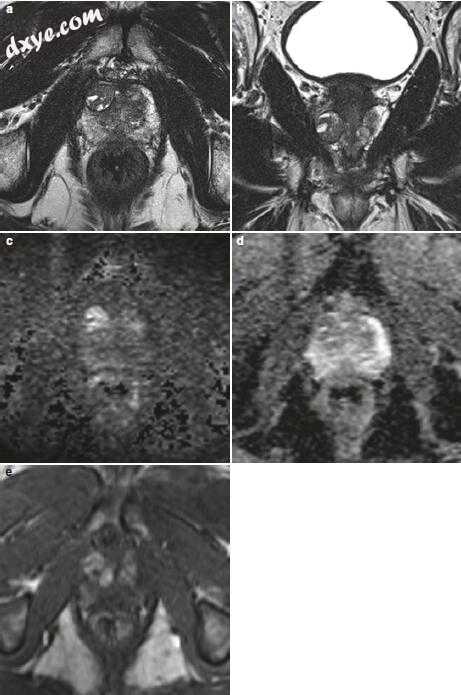

图11.11(a-e)周边区域的PI-RADS 5病变。 (a)轴向和(b)冠状T2加权序列,显示右侧外周区域中的外接18mm低信号质量(PI-RADS评分5)。 (c)扩散加权高b值(计算b = 1400s / mm2)图像显示质量的焦点显著高信号强度。 (d)ADC图(周边区域的显性序列)相应地显示质量的焦点显著低信号强度(PI-RADS评分5)。 (e)DCE序列显示局灶性和早期增强(DCE阳性)对应于在T2加权和DWI上观察到的局灶性质量,与总体PI-RADS评分为5一致.MRI / US融合引导活检显示Gleason 4 + 3 = 7腺癌(PSA水平为11.2ng / mL)。还要注意左侧外围区域中的楔形T2低信号,其在ADC图上显示中度低信号并且没有焦点增强(PI-RADS 3)。在活检多灶性前列腺癌中,左前列腺叶被诊断为Gleason 3 + 3 = 6型